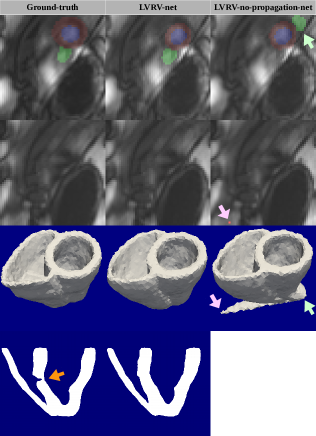

To better understand the role of propagation as well as the robustness achieved by the LVRV-net, we look at the cases for which different methods have extremely contrasting performances, and define that the LVRV-no-propagation-net fails while the LVRV-net succeeds on a stack, if the latter outperforms the former on Hausdorff distance by a large value , for any of the 4 structures (LVM, LVC, LV-epi, and RVC). And vice versa. For illustration, we use =30mm, but similar interpretations can stand for other values of . In Fig.6 we present three typical examples out of the 73 stacks in the UK Biobank testing set for which the LVRV-no-propagation-net fails while the LVRV-net succeeds. In the first example, on the one hand, the apex is so faint on the apical slice that it is barely possible to determine its size precisely. The ground-truth apex seems to be somewhat too large while the LVRV-net prediction looks a little bit too small (in a way learned from the training set with ground-truth variability). But the LVRV-net prediction still well determines the location of the apex using the contextual information. On the other hand, there is a structure on the slice of appearance very similar to the heart. The LVRV-no-propagation-net is confused by it and hence makes a completely wrong prediction. If we reconstruct the anatomical mesh of the heart based on the segmentation (to overcome the problem of large slice thickness, we apply interpolation to generate the segmentation on the intermediate slices between two adjacent slices), the mesh reconstructed from LVRV-no-propagation-net is clearly wrong on the apex. Similarly, the LVRV-no-propagation-net misses the right structure and/or makes a false positive prediction. In contrary, LVRV-net fails while LVRV-no-propagation-net succeeds on only 10 stacks. For 7 of them, LVRV-net predicts a tiny false positive component on a slice either below the apex or around the base. These failures may be simply fixed via the removal of all but the largest connected components. For the other 3 stacks, the errors are caused by image quality problems including large artifact on image and serious misalignment between adjacent slices.

The authors of [16] propose a method achieving human-level MRI analysis on UK Biobank. They aim at segmenting as accurately as possible each slice, in contrast with our method, which focuses on the consistency of segmentation across slices. Though the results of their method and that of ours are not directly comparable due to the differences on metrics (e.g. 2D Hausdorff Distance vs 3D Hausdorff Distance), training/testing datasets, preprocessing methods, etc., [16] inspired us to compare the performance of our method with that of human experts in terms of 3D consistency, which is the main focus of our method. In Fig.6, for each example, we present a slice of the long-axis view (the last row) for both meshes reconstructed from the ground-truth and the LVRV-net prediction. As indicated by the arrows, with qualitative comparison we find that among these pairs of meshes the ground-truth reconstruction meshes are less regular and less smooth. It suggests that our method maintains 3D consistency even better than human experts.